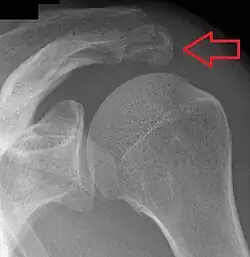

Shoulder

.jpg)

- An os acromiale forms when any of its four ossification centers fail to fuse. These four ossification centers are called (from tip to base) pre-acromion, meso-acromion, meta-acromion, and basi-acromion. In most cases, the first three fuse at 15–18 years, whereas the base part fuses to the scapular spine at 12 years. Such failure to fuse occurs in between 1% and 15% of cases.[23][24] It rarely causes pain.